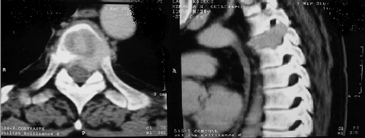

Por dolor intenso a nivel de columna dorsal se estudió con Tomografía Axial Computarizada y Resonancia Magnética (Figura 4), las que mostraron proceso infiltrativo a nivel de la vértebra T4, que desplaza la médula realizándose fijación de columna dorsal a este nivel. Biopsia compatible con tumor pardo (Figura 4).

Figura 4. Resonancia magnética de columna dorsal muestra proceso infiltrativo a nivel de T4, que desplaza la médula.